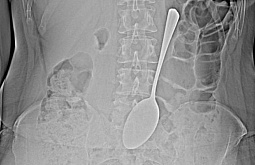

Жительница Бурятии проглотила ложку длиной 18 см

Здоровье, 03.12.2025

Хирургической операции удалось избежать